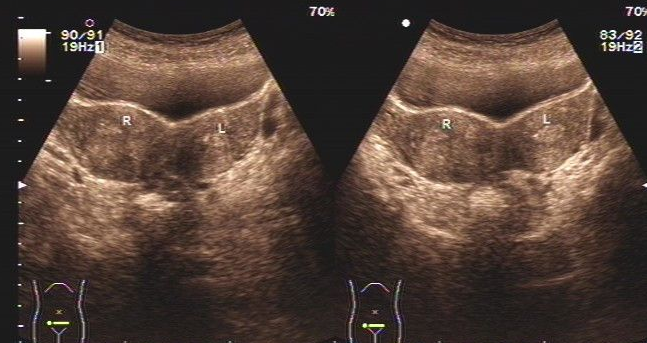

双侧多囊卵巢

而且b超显示小张双侧卵巢体积偏小,回声偏实.最终